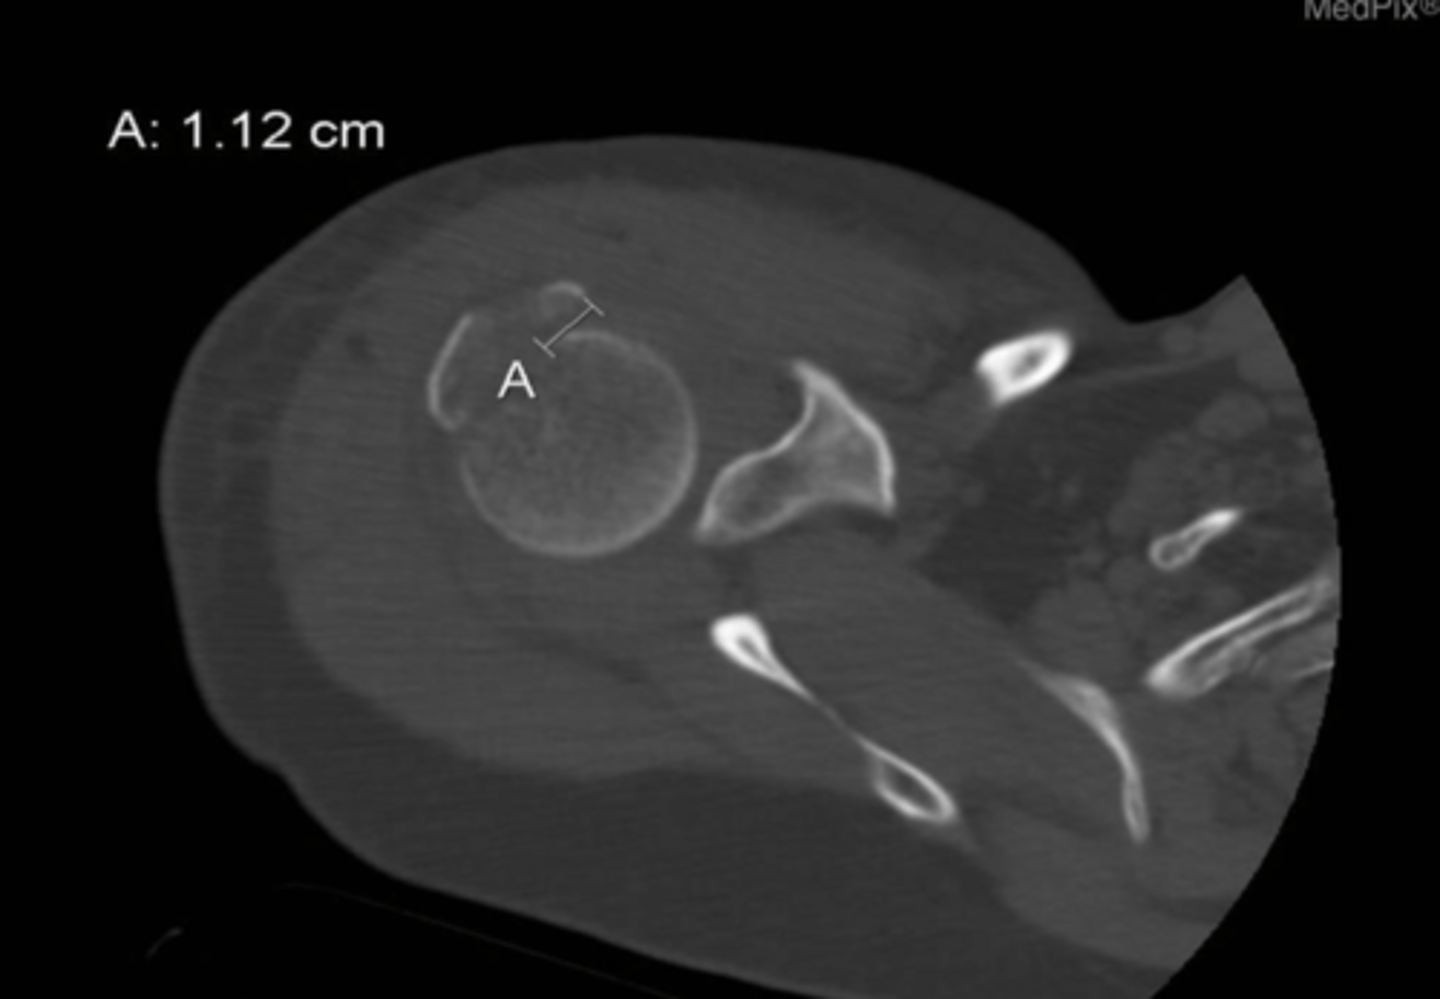

displacement

What is identified by A in this image?

a. edema

b. displacement

c. bruising

d. osteophyte